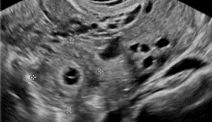

Sandsynlig ektopisk graviditet

Inhomogent adnexalt ("blob") eller ekstracavitært tomt sæk‑lignende strukturer, fri væske.

På dansk: Mulig men ikke sikker graviditet udenfor livmoderen.